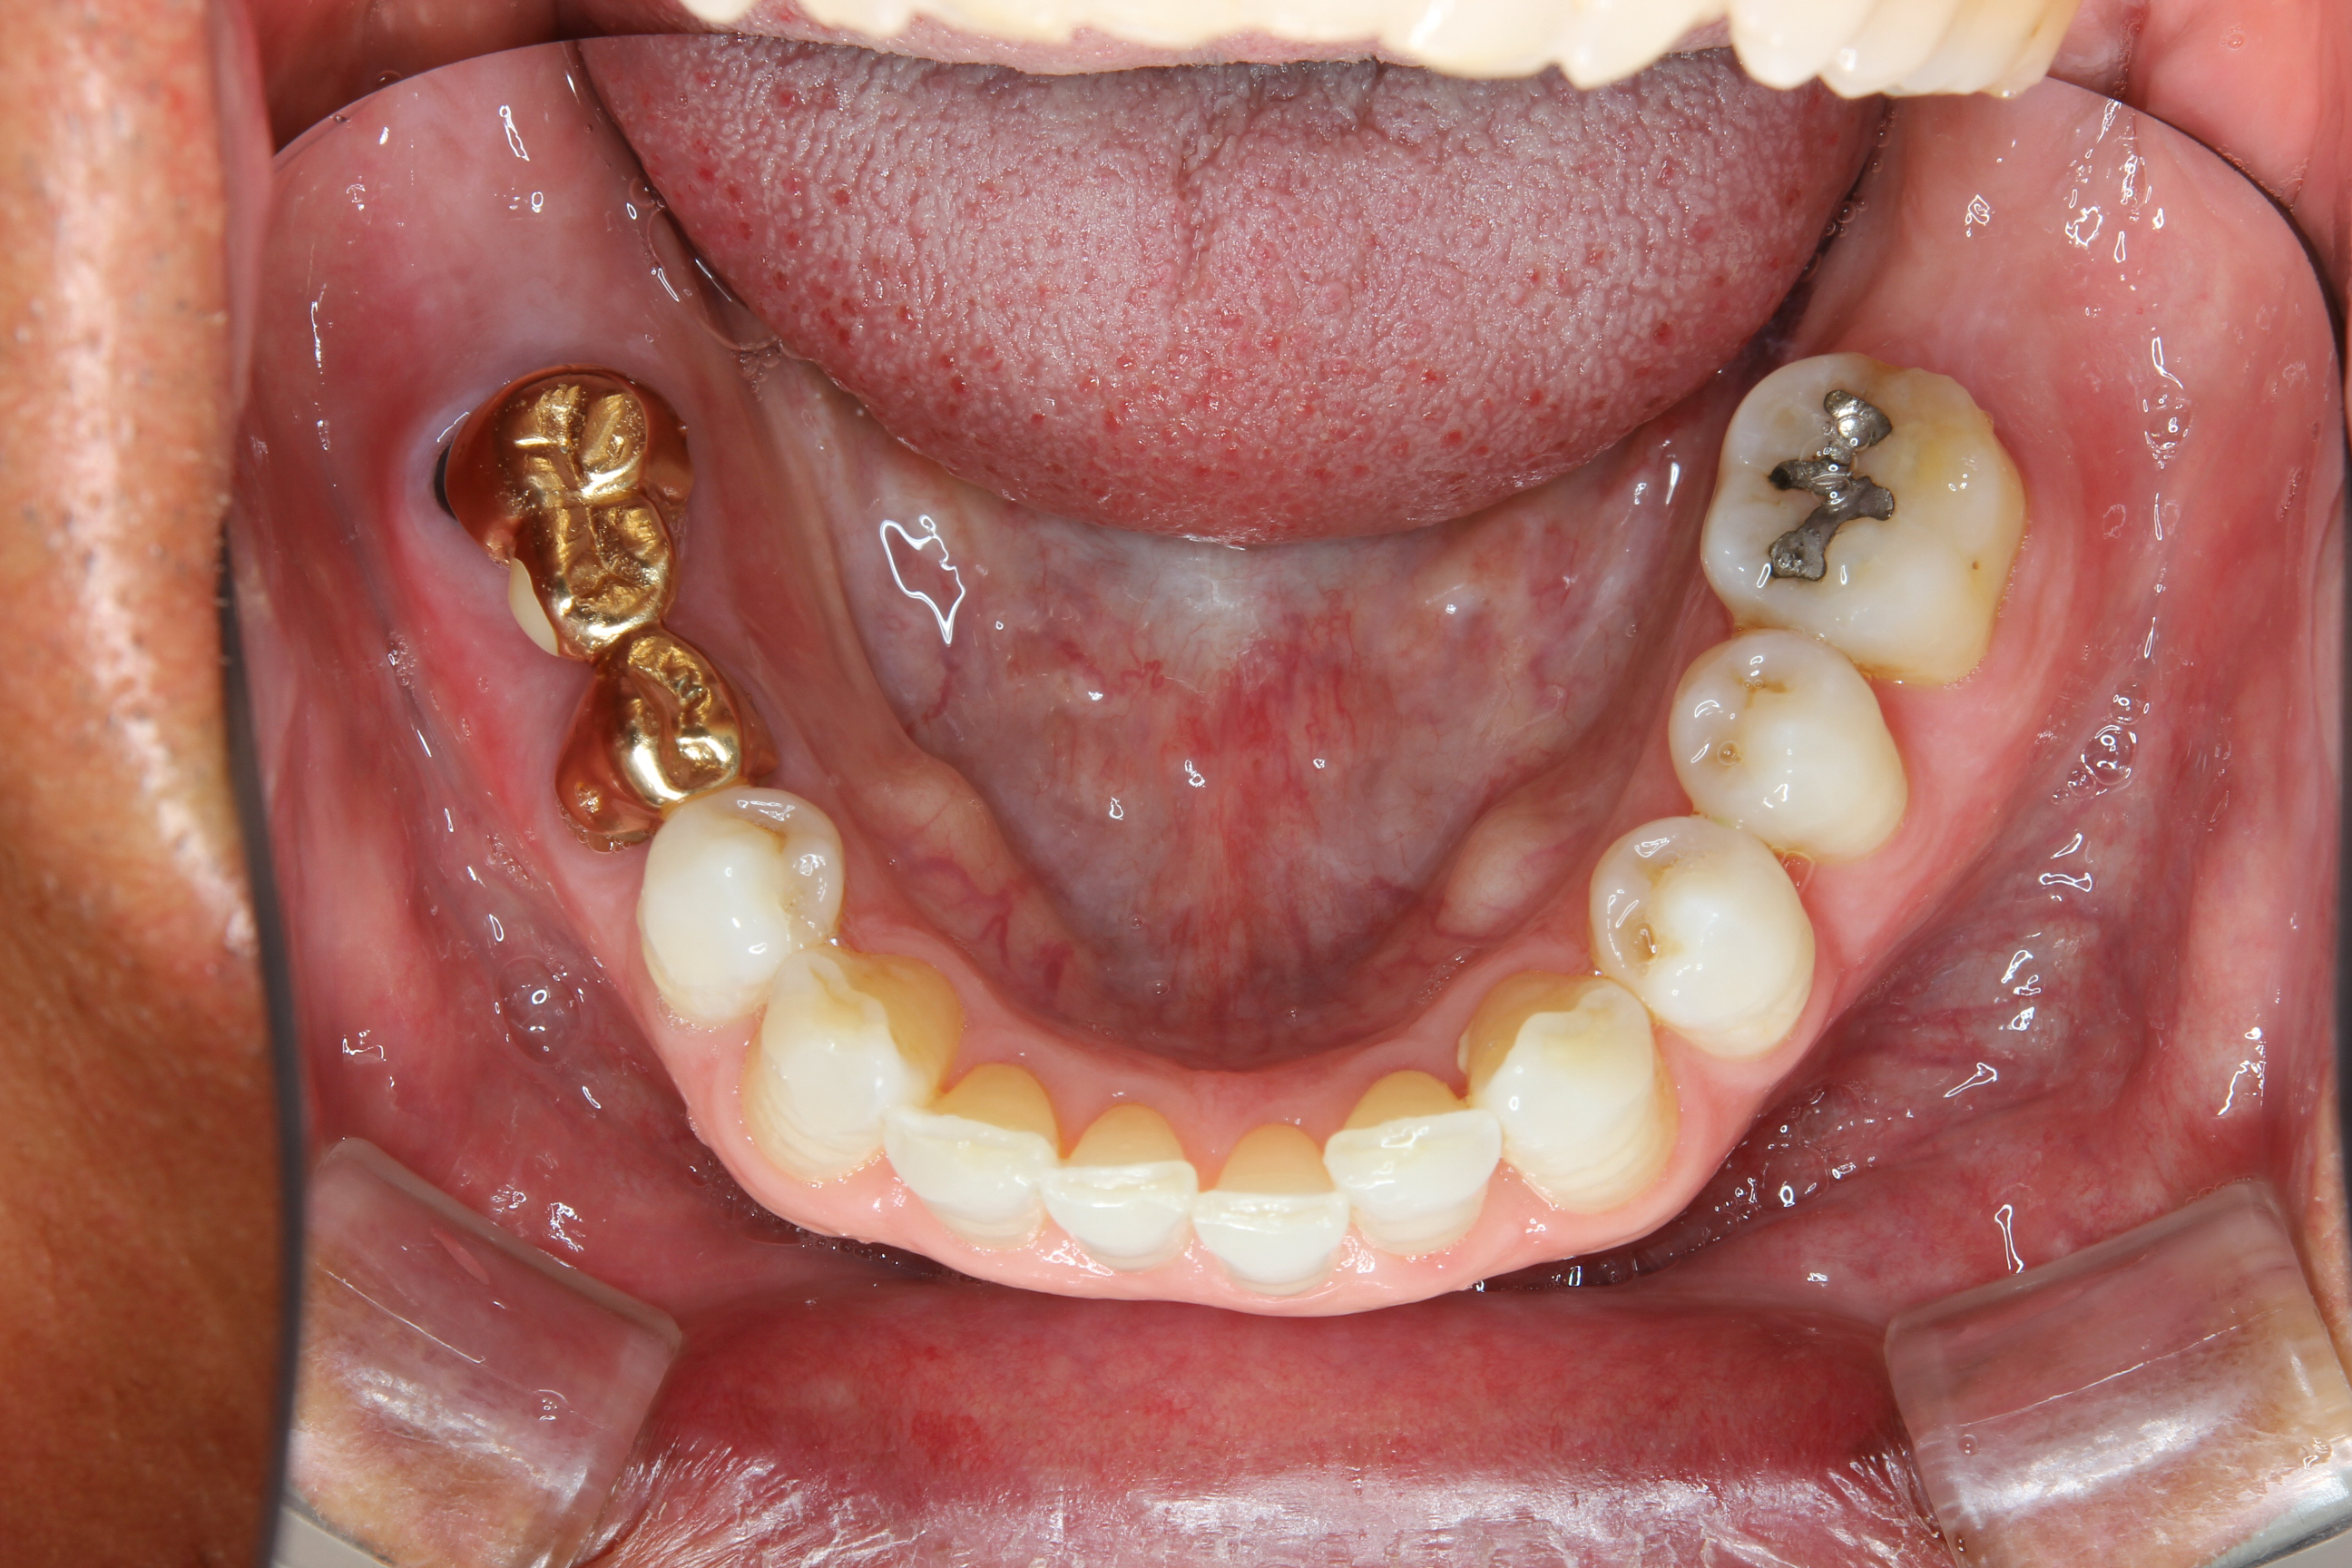

まず、右下ブリッジの支台歯には根尖病巣が認められたので根管治療を行いました。

そして、左右の欠損部にはインプラントを埋入しました。

その後、インプラントと噛み合わせる歯が挺出してしまっているので形態の調整を行い、インプラントに仮歯を装着。

噛み合わせのバランスを整えます。

インプラントにて歯を取り戻すことにより、対合歯の挺出は抑えられるのです。

最終的な被せ物を装着するにあたっては、患者さんは審美的でクオリティーの高いものを希望されていたので、全体のホワイトニングを行い、下顎の歯はメタルセラミックスクラウンやブリッジによる治療を行いました。

また、正中のコンポジットレジンを改善し、前歯や歯間部の形態を整えました。

上顎右側第2大臼歯(最後方歯)は、対合歯であるインプラント上部構造の破折等に配慮し、ゴールドクラウンを用いました。

下の写真が治療後です。

きれいになった口腔内を写真で見て、患者さんも喜んでくれました。

最後方の奥歯を取り戻すには、やはりインプラントは有用ですね。